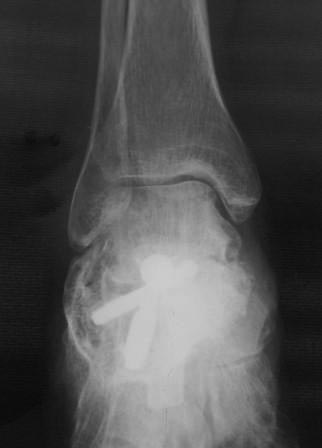

Уважаемые коллеги. Вчера госпитализирован пациент 1970г.р. , в ноябре 2014г, получил о/перелом пяточной кости. в другой клинике произведена КДО аппаратом Илизарова, после трех месяцев аппарат сняли? , и больной начал наступать и ходить?- все это со слов б-ного(р-снимков нет.), Жалобы боли при ходьбе к-рая в динамике усиливается, об-но: деформация пяточной кости, движение в г/стоп.суставе почти в польном обьеме, по мед.поверхности пятки рубец плотно спаянный с костью. Предварительный план: корригируюшая остеотомия пяточной кости, для создания свода стопы.( сможем ли опустить бугра пяточной кости из-за натяжения ахиллово сухожилия), и подтаранный артродез. С уважением Абдурашид.

Уважаемый коллега, в случае Вашего пациента положительным моментом является отсутствие деформации пятки в горизонтальной (аксиальный) плоскости, что несколько упрощает остеотомию в планируемой операции. Но надо отметить, что имеется выраженная посттравматическая деформация в сагитальной плоскости со значительным сдвигом места крепления ахиллова сухожилия к переди, что снижает эффективность действия мышц задней группы голени. Моё предложение - клиновидная (с основанием вниз) корригирующая остеотомия бугра пяточной кости, закрытая ахиллотомия. Но, поскольку деформация значительная, стремиться полностью восстановить анатомические ориентиры не стоит. Фиксацию предлогаю Осуществить 2 винтами типа Барука (7,0).

В таких случаях необходимо точно знать причину боли... чаще всего- это латеральный импиджмент (различных степеней) и подтаранный артроз. Исходя из выявленной причины выбирается тактика лечения! Простая попытка восстановить нормальную анатомию будет сложной в исполнении и не даст желаемого результата.

Уважаемые коллеги. Операция была произведена 22.01.16г., только сегодня имеется возможность отправить. L-образный доступ. . при ревизии подтаранный сустав сохранен, поэтому линейная остеотомия, подкожная ахиллотомия. Подготовка ложа, и смещенный отломок спущен вниз к ложу , но до конца не смогли. Фиксирован двумя винтами. По медиальной поверхности рубец плотно спаянный с костным осколком, пока не трогали из-за опасения инфицирования, после заживления раны потом будем думать, что делать.

Аксиальная Р-грамма вышло некачественно, потому что гипс наложен в положении некоторого эквинуса.